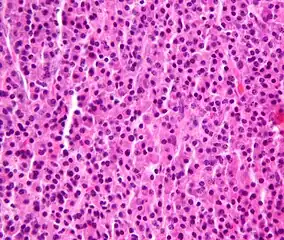

Bone marrow aspirate showing the histologic correlate of multiple myeloma under the microscope, H&E stain -

Plasmacytoma, H&E stain -

Histopathology

A bone marrow biopsy is usually performed to estimate the percentage of bone marrow occupied by plasma cells. This percentage is used in the diagnostic criteria for myeloma. Immunohistochemistry (staining particular cell types using antibodies against surface proteins) can detect plasma cells that express immunoglobulin in the cytoplasm and occasionally on the cell surface; myeloma cells are often CD56, CD38, CD138, and CD319 positive and CD19, CD20, and CD45 negative.[15] Flow cytometry is often used to establish the clonal nature of the plasma cells, which will generally express only kappa or lambda light chain. Cytogenetics may also be performed in myeloma for prognostic purposes, including a myeloma-specific fluorescent in situ hybridization and virtual karyotype.

The plasma cells seen in multiple myeloma have several possible morphologies. First, they could have the appearance of a normal plasma cell, a large cell two or three times the size of a peripheral lymphocyte. Because they are actively producing antibodies, the Golgi apparatus typically produces a light-colored area adjacent to the nucleus, called a perinuclear halo. The single nucleus (with inside a single nucleolus with vesicular nuclear chromatin) is eccentric, displaced by an abundant cytoplasm. Other common morphologies seen, but which are not usual in normal plasma cells, include:

- Bizarre cells, which are multinucleated

- Mott cells, containing multiple clustered cytoplasmic droplets or other inclusions (sometimes confused with auer rods, commonly seen in myeloid blasts)

- Flame cells, having a fiery red cytoplasm[43][44]